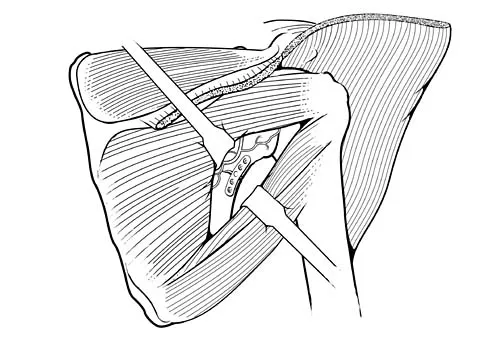

A 42-year-old man sustained a fracture of the distal radius with subsequent stiffness in the ipsilateral shoulder. Despite a 6-month program of range-of-motion exercises, external rotation at the side is limited to 10 degrees. Attempts at closed manipulation are unsuccessful. Treatment should now consist of

When external rotation at the side is limited, the most likely diagnosis is contracture of the rotator cuff interval, including the superior glenohumeral and coracohumeral ligaments. Therefore, the treatment of choice is arthroscopic release of the rotator cuff interval.